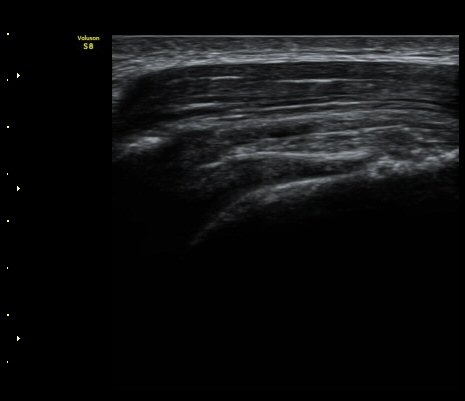

±Ø»ó°Ç Ⱦ´Ü¸é°Ë»ç¿¡¼­ ºÎºÐÀûÀÎ ±Ø»ó°Ç ÀüÃþÆÄ¿­°ú ºÀÇջ簡 °üÂûµÈ´Ù(»çÁø 7, 8)